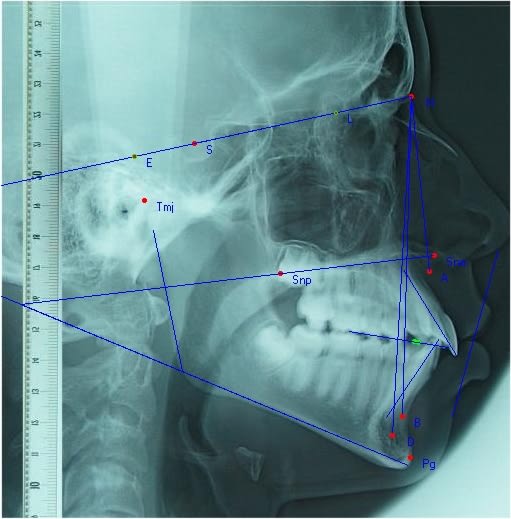

Analyse céphalométrique Florent

Analyse de Steiner

SNA 82 84 position correcte A

SNB 80 76 retroposition point B

ANB 2 8 tres augmenté par recul de B

SND 76 74.5 Mandibule en position normale

II/NB 25 32.5 Protrusion Inc inf.

UI/NA 22 26 Protrusion Inc sup

IntII 130 115 Angle InterIncisif tres diminué

CrMb 32 35 Rotation normale Mb a tendance hyperdiv

Cr Occ14 21 Inclinaison post plan occlusion

esth 180 150 Profile convexe

Holdaw1 7 Altération plan facial inférieur

Savoir évidemment faire et interpréter une analyse avec humilité.

Ici dans l'analyse de Steiner, le plan de référence est SN , S etant le centre de la selle turcique. SN est critiqué comme ne permettant pas une visualisation clinique facile.

Et puis, il y a les zones difficilement identifiables sur la cephalo.Ici, g eu du mal a bien voir la rotondité condylienne et les contours précis de la partie antérieure de l'épine nasale.

Demain, occlusion, analyse ricketts

Et le fichier graphique joint.

Florent steiner a2osui - Eugenol